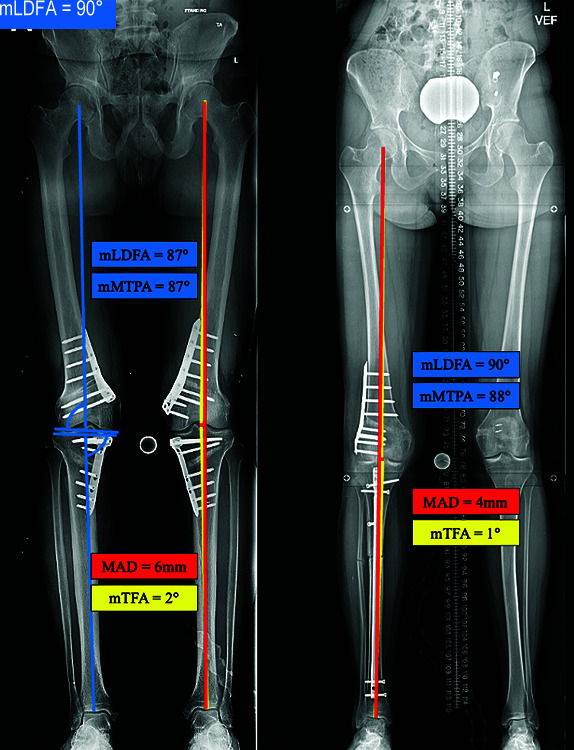

Results: The mean mechanical axis deviation (MAD) correction was 56 mm for varus deformities (n = 13) and 45 mm for valgus deformities (n = 8) with an overall mean correction of the femoral tibial angle of 15° per extremity. The accuracy of correction was 92.9% compared to the goal MAD. Two patients had peri-incisional cellulitis that resolved with antibiotics. There was no incidence of non-union, deep vein thrombosis, compartment syndrome, deep infection, or peripheral nerve palsy. Patient-reported outcome scores had clinically meaningful improvements in pain, function, and mental health.